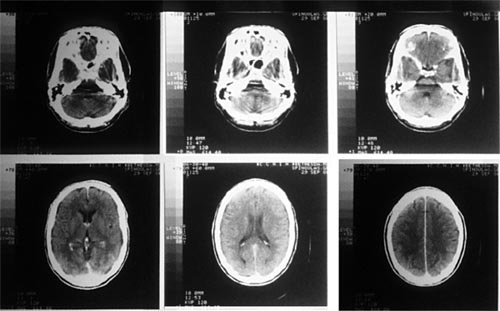

CT掃描儀用X射線作為掃描光線,跟傳統(tǒng)的X光掃描不同的是CT掃描儀不只是拍攝一張圖片,而是會(huì)拍攝不同截面的多張圖片,之通過系統(tǒng)將拍攝的圖片合成完整的三維圖像,恢復(fù)被掃描的內(nèi)部結(jié)構(gòu)。

傳統(tǒng)X射線最大的局限在于,傳統(tǒng)的X射線只能提供二維的圖片,因此無法提供器官或身體其他部位內(nèi)部結(jié)構(gòu)的具體信息,真實(shí)反映出檢測(cè)部位的三維結(jié)構(gòu)。此外,人體許多不同的組織對(duì)X射線有相近的吸收能力,導(dǎo)致無法通過X射線區(qū)分這些不同的組織。并且在傳統(tǒng)的X射線檢測(cè)中,會(huì)有大量的射線被散射掉,導(dǎo)致圖像很不完整。而CT掃描不僅可以提供被檢測(cè)部位內(nèi)部結(jié)構(gòu)的三維圖像,還可以區(qū)分不同的組織,并將X射線集中在特定的檢測(cè)區(qū)域,從而得到更清晰的圖像。